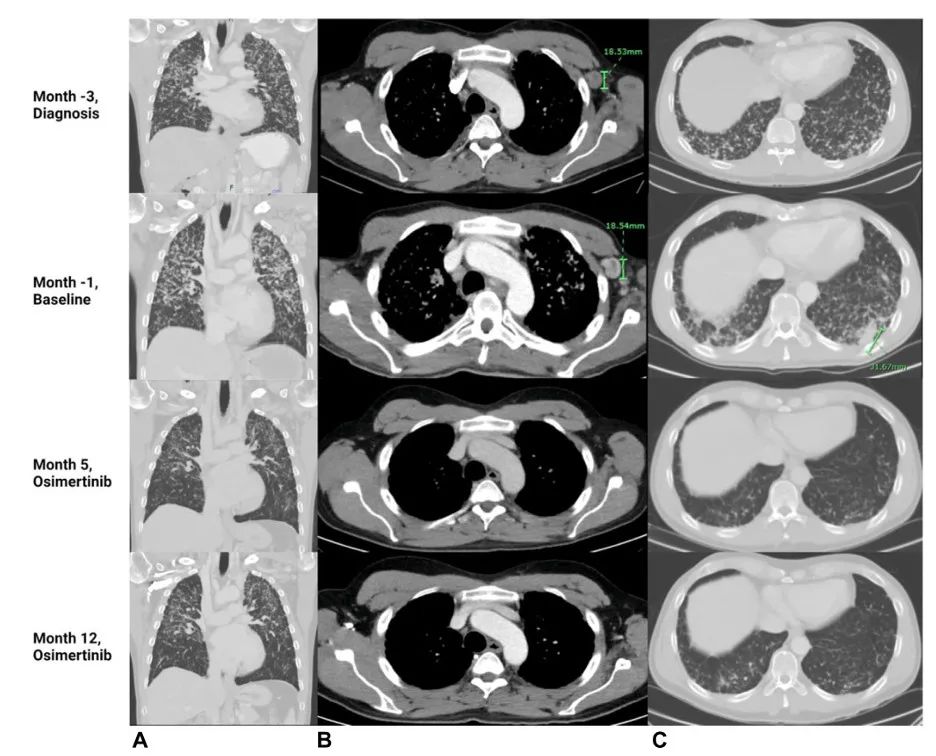

图2.在诊断、基线(化疗+免疫治疗进展时间)、奥希替尼治疗第5个月和奥希替尼治疗第12个月时(A)肺、(B)腋窝淋巴结和(C)肺基底部的CT图像。影像学检查显示疾病(弥漫性实质性肺疾病、左腋窝淋巴结肿大和肺基底部结节)缓解。

使用FoundationOne Liquid CDx再次进行NGS检测,结果显示等位基因频率为0.38%的EGFR-RAD51基因融合。患者的治疗方案从化疗+免疫疗法改为每日80 mg奥希替尼。1个月内,患者的症状明显改善。三个月后,患者重返工作岗位,体重恢复到基线水平。视觉症状和癌症相关的疼痛已经解决。影像学检查显示肺部结节、淋巴结肿大和骨转移的骨硬化有所改善。9个月时,发现无症状颅内转移瘤且全身性疾病稳定。

在最后一次随访中,即开始奥希替尼治疗约一年后,影像学检查继续显示部分缓解,迄今为止他仍在接受治疗。